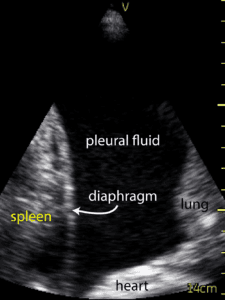

The TUS images of the pleural effusions were classified by previously published criteria [6,7]. Anechoic was defined by no echoes present between the visceral pleural and diaphragm. Complex, nonseptated was defined by an increased echogenicity of the space between the visceral pleura and diaphragm, without clear hyperechoic linear findings to suggest septation. Complex, septated was defined as echogenic linear structures presenting in the space between the visceral pleura and diaphragm. Homogenously echogenic was defined as echogenic material filling the entire space between pleural and diaphragm. Figure 1. demonstrates representative imaging.

Figure 1. Sample pleural fluid images. 0, anechoic – no echoes present between the pleura and diaphragm; 1, complex, non-septated – increased echogenicity of the space between the pleura and diaphragm, without clear hyperechoic linear findings to suggest septation; 2, complex, septated – echogenic linear structures present in the space between the pleura and diaphragm; 3, homogenously echogenic – echogenic material filling the entire space between the pleura and diaphragm.